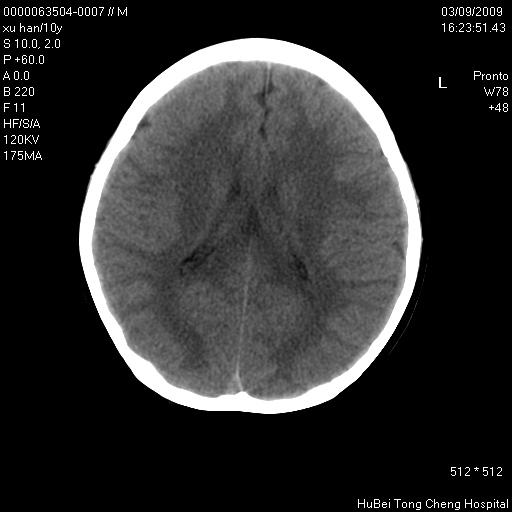

以下是引用道哥在2009-3-9 18:40:00的发言:[br]未见明显异常,必要时mr(dwi)成像。

以下是引用余辉在2009-3-10 11:01:00的发言:[br]考虑双侧海马急性缺氧性损伤